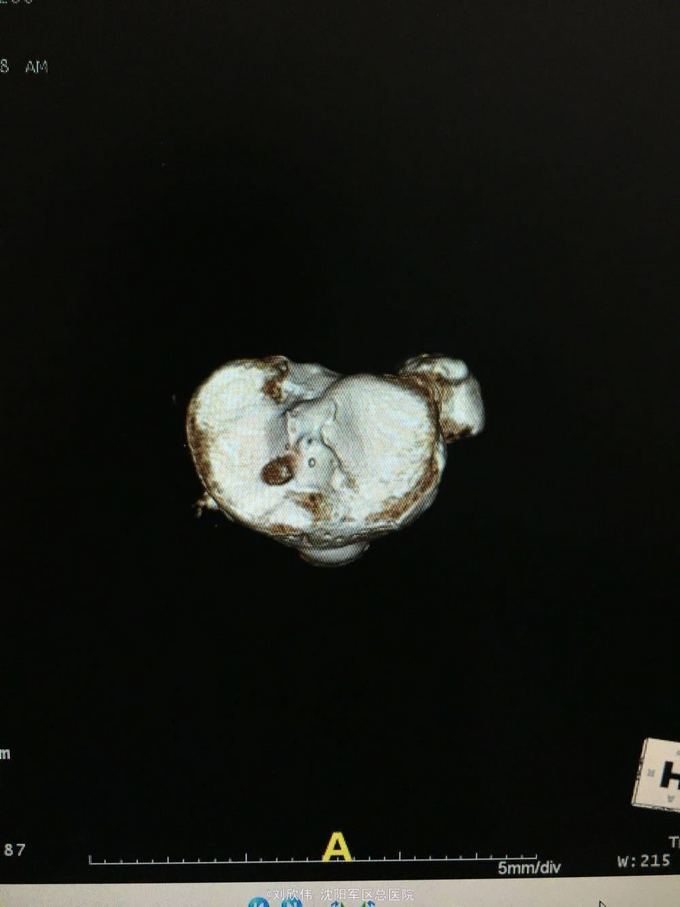

关节镜之前交叉韧带+内侧副韧带损伤1例

男性,44岁,摔伤所致,左膝。诊断如题

前抽屉,lachman,轴移阳性,外侧应力试验因疼痛无法进行

诊断如题,关节镜解决acl,mcl给予支具保守治疗

这个病例值得讨论的有2点,其一,mcl即内侧副韧带的处理通常可以保守治疗,二期不稳后再行手术治疗。第二,前叉胫骨侧隧道内口的位置,一个原则,宁内勿外。